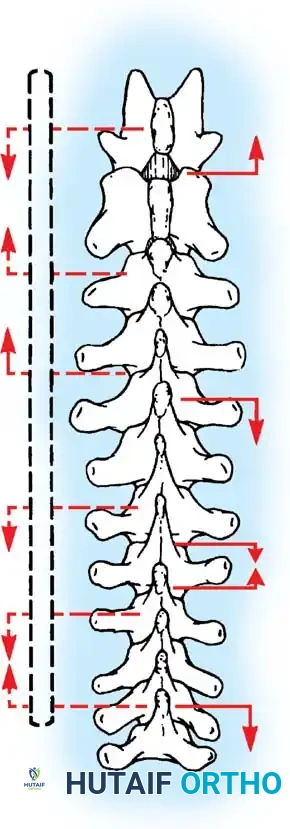

Posterior Surgeries for Idiopathic Scoliosis: A Masterclass in Surgical Technique

Key Takeaway

The posterior approach remains the workhorse for the surgical correction of adolescent idiopathic scoliosis. It provides extensile, safe access to the entire vertebral column, facilitating multi-segmental instrumentation and robust arthrodesis. Success relies on meticulous patient positioning to preserve sagittal alignment, precise subperiosteal exposure to minimize blood loss, and rigorous facetectomy and decortication to ensure a solid, long-lasting spinal fusion.

Bone graft incorporates most effectively under compressive loads and is biologically disadvantaged in environments of distraction. Therefore, in scoliosis correction, if autogenous bone is limited, it should be preferentially concentrated on the concave side of the curve, which is subjected to compressive forces, rather than the convex side, which experiences tension. Furthermore, the farther the fusion mass is placed from the instantaneous axis of rotation, the more effectively it will neutralize movement across that axis.